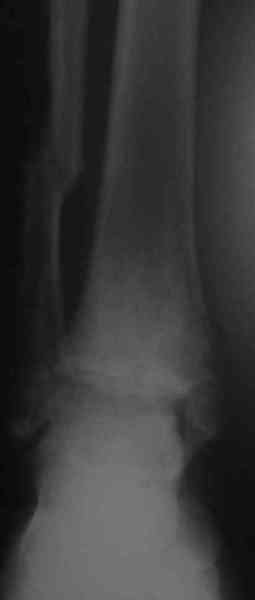

На консультацию обратилась пациентка, 26лет. В 2002 году открытый переломо-вывих. Лечение: вправление, трансфиксация спицами и гипсовая повязка. Около 4-х месяцев сохранялись явления нагноения вокруг спиц. На сегодня - движения в суставе отсутствуют, постоянные боли, функциональное укорочение конечности = 3 см.